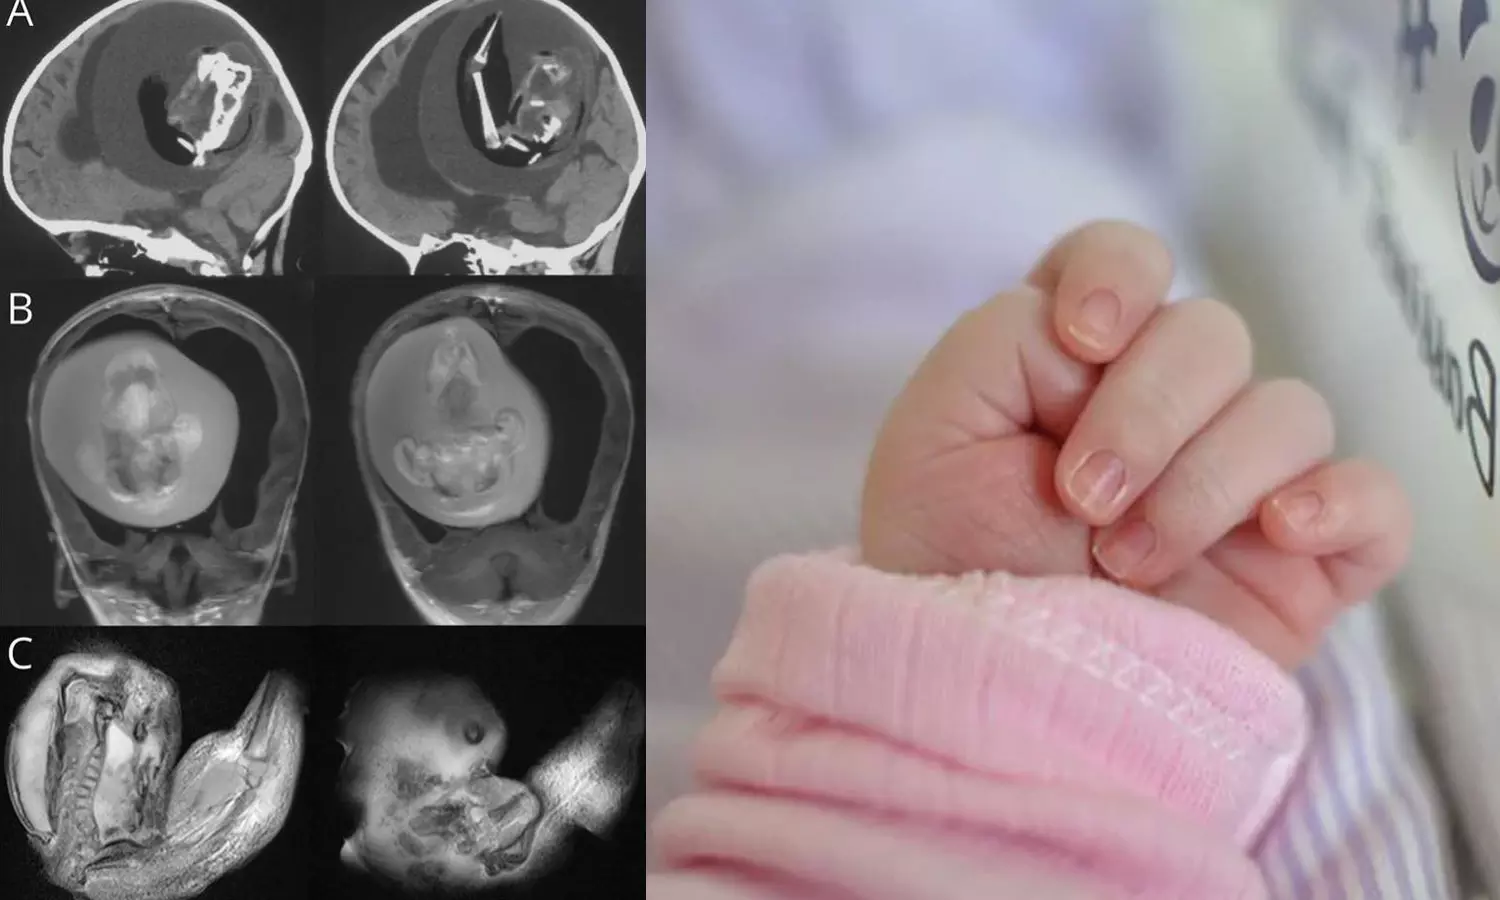

ബെയ്ജിങ്: ഒരു വയസുള്ള കുഞ്ഞിന്റെ തലച്ചോറിനുള്ളിൽ ഇരട്ടയുടെ ഭ്രൂണം. കേൾക്കുമ്പോൾ അതിശയം തോന്നുന്നുണ്ടോ?. എന്നാൽ വിശ്വസിച്ചേ പറ്റൂ. ചൈനയിലാണ് സംഭവം. ഒരു വയസ് മാത്രം പ്രായമുള്ള കുഞ്ഞിന്റെ തലച്ചോറിനുള്ളിൽ നിന്ന് ഇരട്ടയുടെ ഭ്രൂണം നീക്കം ചെയ്തതായി ഷാങ്ഹായിയിലെ ഡോക്ടർമാർ പറഞ്ഞു. ന്യൂറോളജി ജേണലിൽ പ്രസിദ്ധീകരിച്ച ഒരു പഠനത്തിലാണ് ഇക്കാര്യം വ്യക്തമാക്കുന്നത്.

തല വലുതായ കുഞ്ഞിനെ ആശുപത്രിയിൽ പ്രവേശിപ്പിച്ചപ്പോൾ നടത്തിയ സ്കാനിങ്ങിലാണ് ഞെട്ടിക്കുന്ന വിവരം അറിഞ്ഞത്. ഇരട്ടയുടെ ഭ്രൂണത്തിന് കൈകാലുകളും എല്ലുകളും വിരലുകൾ പോലെയുള്ള മുകുളങ്ങളും വികസിച്ചതായി ഡോക്ടർമാർ പറഞ്ഞു.

ഇൻട്രാവെൻട്രിക്കുലാർ ഫീറ്റസ്-ഇൻ-ഫീറ്റൂ എന്നറിയപ്പെടുന്ന ഈ അവസ്ഥ ഗർഭാശയത്തിൽ ഇരട്ടകൾ കൂടിച്ചേരുമ്പോഴാണ് സംഭവിക്കുന്നതെന്ന് ഡോക്ടർമാർ പറയുന്നു. 'എന്നാൽ ഒന്നിന്റെ വളർച്ച മാത്രമേ കൃത്യമായി നടക്കുന്നുള്ളൂ'- മിയാമി ഹെറാൾഡ് റിപ്പോർട്ട് ചെയ്തു. ഒരു കുട്ടിയുടെ വയറ്റില് മറ്റൊരു ഭ്രൂണം വളരുന്ന അവസ്ഥയാണിതെങ്കിലും ചിലപ്പോഴൊക്കെ അത് തലച്ചോർ ഉൾപ്പെടെയുള്ളവയിലും ആവാം.

ഭ്രൂണത്തിന്റെ ജീനോം സീക്വൻസിങ് ഇത് ഒരു വയസുള്ള കുഞ്ഞിന്റെ ഇരട്ടയാണെന്ന് കണ്ടെത്തിയതായി പഠനം പറയുന്നു. ഇത്തരം കേസുകൾ ലോകത്ത് വളരെ അപൂർവമായി മാത്രമേ കാണപ്പെടുന്നുള്ളൂ, 10 ലക്ഷം കുട്ടികളിൽ ഒരാൾക്ക് മാത്രമേ ഇത് സംഭവിക്കൂ.